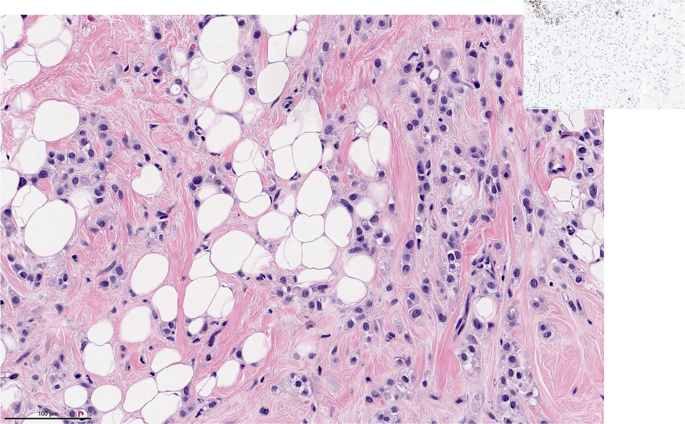

Invasive ductal carcinoma of no special type - medullary pattern

With the 5th Edition of the WHO Classification, medullary carcinoma ceased to be considered a distinct subtype of breast cancer and was classified as a pattern within invasive ductal carcinoma of no special type5. Relatively high interobserver variability and overlap with basal-like tumors and breast cancers seen in patients with deleterious germline BRCA1 pathogenic variants, led to the reassignment of this group of tumors in the most recent WHO classification5,6. This group of tumors is characterized by high grade features, dense lymphocytic infiltrate and are often well circumscribed (Fig. 2). Previous literature on this breast cancer subtype found that they have a favorable prognosis relative to invasive ductal carcinomas no special type7, and that they are responsive to chemotherapy8. These tumors are over-represented in the immunomodulatory subgroup of TNBCs9. Their excellent prognosis and responsiveness to therapy, relative to TNBCs of similar size receiving the same therapy, may place them in the group of tumors for which de-escalation studies may be considered10.

Morphologic features include high grade histology, syncytial architecture with no glandular structures, pushing margins, and prominent tumor infiltrating lymphocytes. (The term “syncytial growth” refers to a growth pattern characterized by broad, confluent bands of tumor cells more than five cells thick, often with indistinct cell borders77). Previously, described as “medullary carcinoma”, “atypical medullary carcinoma”, or “carcinoma with medullary features”, it is no longer classified as a special histologic subtype of invasive carcinoma according to the current WHO Classification. It is rather considered part of the spectrum of invasive carcinoma no special type, representing one end of the spectrum of the tumor infiltrating lymphocyte rich invasive carcinomas. H&E stain. Magnification 200x.